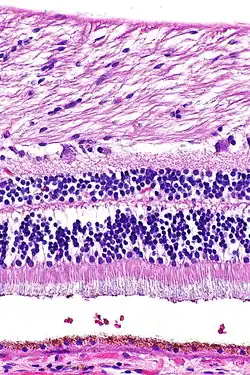

H&E stain

H&E is the combination of two histological stains: hematoxylin and eosin. The hematoxylin stains cell nuclei a purplish blue, and eosin stains the extracellular matrix and cytoplasm pink, with other structures taking on different shades, hues, and combinations of these colors.[5][6] Hence a pathologist can easily differentiate between the nuclear and cytoplasmic parts of a cell, and additionally, the overall patterns of coloration from the stain show the general layout and distribution of cells and provides a general overview of a tissue sample's structure.[7] Thus, pattern recognition, both by expert humans themselves and by software that aids those experts (in digital pathology), provides histologic information.

Hematoxylin principally colors the nuclei of cells blue or dark-purple,[6][15][14] along with a few other tissues, such as keratohyalin granules and calcified material. Eosin stains the cytoplasm and some other structures including extracellular matrix such as collagen[5][7][14] in up to five shades of pink.[8] The eosinophilic (substances that are stained by eosin)[5] structures are generally composed of intracellular or extracellular proteins. The Lewy bodies and Mallory bodies are examples of eosinophilic structures. Most of the cytoplasm is eosinophilic and is rendered pink.[10][15] Red blood cells are stained intensely red.